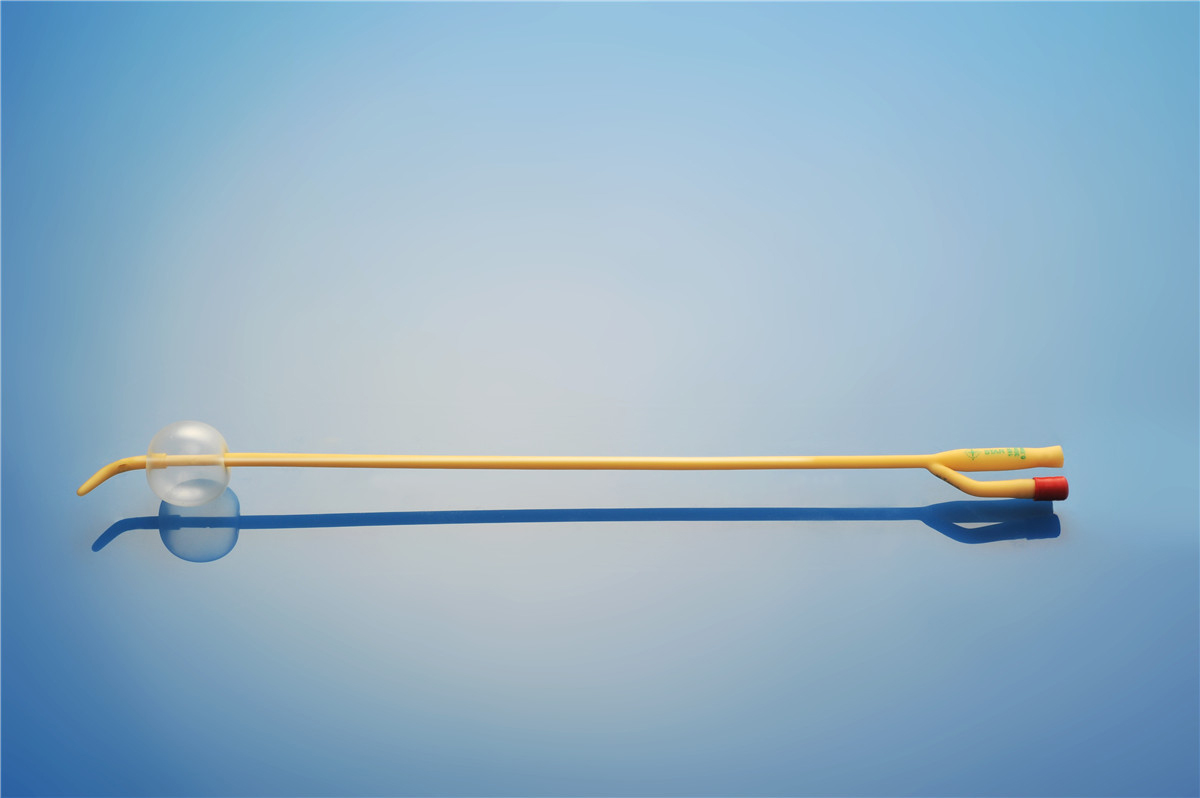

【產品名稱】一次性使用無菌導尿管(取樣型使用) 【型號】雙腔彎頭取樣型 【規格】:12FR-18FR 【主要結構����、性能】由膠乳為主要原材料制成,可配卡片���。

型號:雙腔氣囊彎頭型規格:雙腔氣囊彎頭型:12Fr(5-10mL)���、14Fr(5-10mL)����、16Fr(5-10mL)���、16Fr(30mL)�、18Fr(30mL)����;結構及組成/主要組成成分:產品由導尿管、水潤滑包(選配)組成。雙腔由球囊腔充起錐形接口�、排液腔錐形接口、閥門����、管身、球囊�、排液孔組成(尖端有普通尖頭和彎頭區...